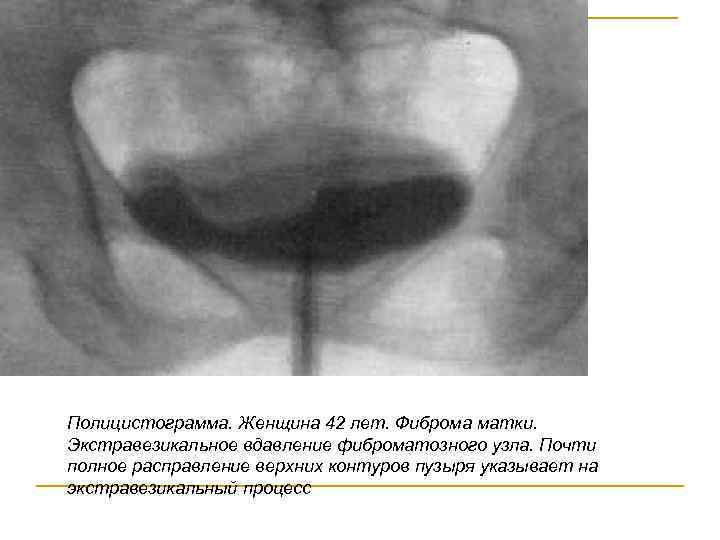

Полицистограмма. Женщина 42 лет. Фиброма матки. Экстравезикальное вдавление фиброматозного узла. Почти полное расправление верхних контуров пузыря указывает на экстравезикальный процесс